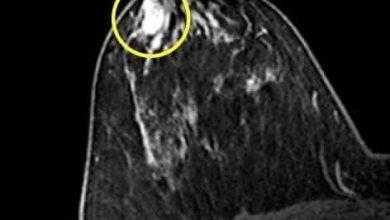

الوَرَم الحُلَیمي القَنَوي Duct papilloma

الوَرَم الحُلَیمي القَنَوي Duct papilloma: وھو ورمٌ حميد داخل قَناة الثدي (الأنبوب الذي ينقل الحلیبَ من الغدَّة إلى الحلمَة)، يسبِّب…